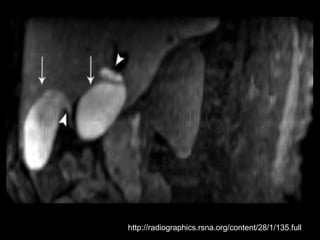

Duplicação da Vesícula Biliar

Ocorre em 0,025% da população;

Causada pela revacuolização incompleta da

vesícula biliar primitiva, que resulta na

persistência de um septo longitudinal.

A cavidade de cada vesícula precisa ter seu próprio

ducto cístico.

A maioria dos casos de duplicação relatados inclui

um quadro de colecistite com cálculos.

Várias condições podem simular vesícula

duplicada.

Exemplos: VB dobrada, VB bilobada, cisto de

colédoco, líquido perivesicular, divertículo da VB,

VB atravessada por feixe vascular e

adenomiomatose focal;

Complicações: torção, papiloma, carcinoma,

obstrução do ducto comum e cirrose biliar;

Foram relatadas vesículas triplas e quádruplas!!!